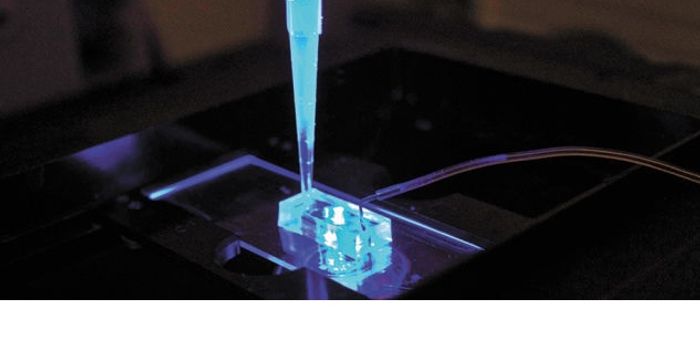

FEB 13, 2016Clinical & Molecular DXImagine a nanoscale needle that can pierce cells precisely and on command. Scientists from Harvard’s Wyss Institut ...